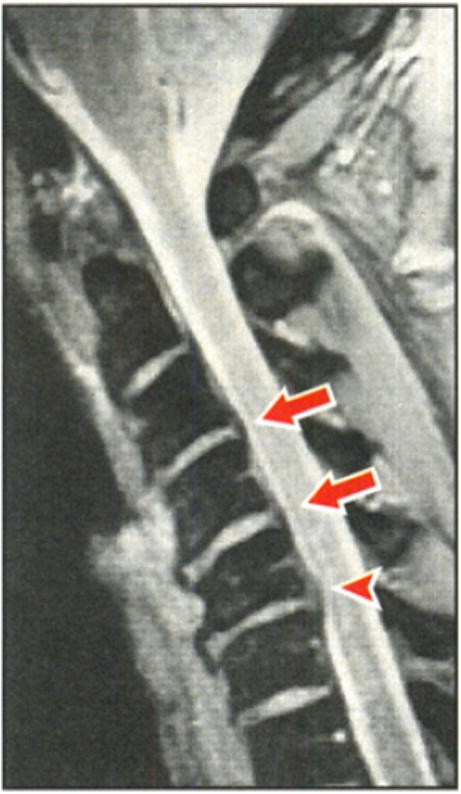

Cervical Sports Injuries The Stinger

Burners Stingers Syndrome Physiopedia